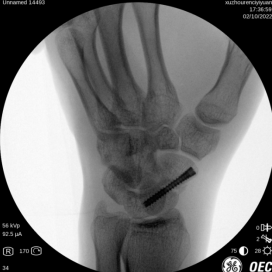

术中摄片

唐医生使用天玑骨科机器人辅助手术,精准定位,避免反复穿刺导致的二次损伤,大大缩短手术时间,术后促进骨质愈合,仅手腕处一个钉眼大小的伤口。